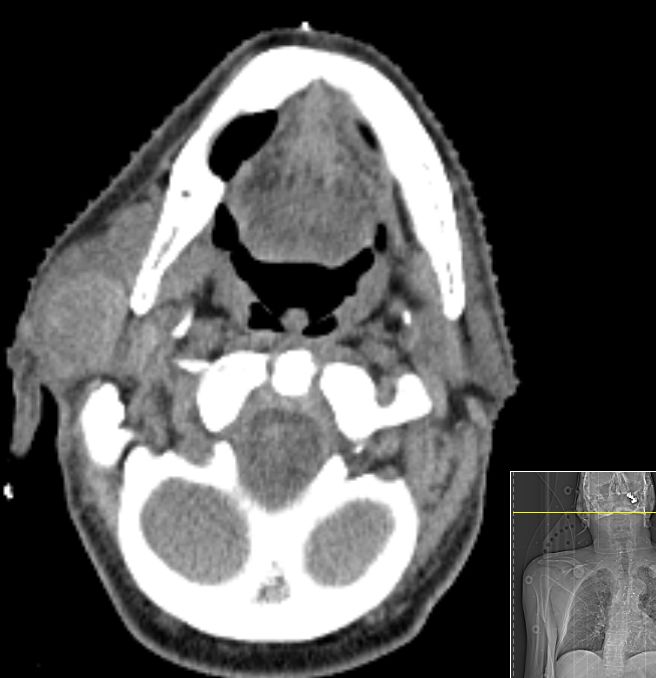

OP-Befund: Rechts eine 30x50 mm messende ballotierende verschiebliche indolente Raumforderung in der Parotis.

Verbreiterter und abgeflacht imponierenden dorsal verlagerter Facialisstammes unter der großen Raumforderung.

Die Raumforderung lässt sich völlig unproblematisch aus dem angrenzenden Parotisgewebe isolieren.

Teilweise ist der Facialis in seinem Mundastbereich platt gewalzt, fächerförmig aufgefiedert, kaum identifizierbar.

Der temporofaciale Ast zieht kaudal und dann ventral der Tumorbildung, die Bifukation ist kaudal des Tumores aufzufinden.